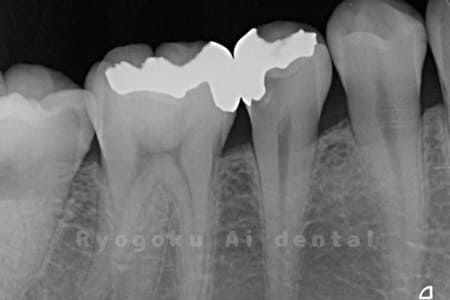

Case01

-

虫歯を徹底的に除去します

感染している神経を除去し、洗浄・消毒

MTA(薬)を置きます

- 原因

- C3、インレー不適合

- 治療期間

- 1ヶ月

- 治療内容

- 断髄治療

- 治療費用

- 88,000円

虫歯の治療と銀歯のやり直しを希望され、銀歯を外したところ、虫歯が大きく、神経の処置が必要と判断。患者様と相談し、神経を残す断髄治療となったケース。

<リスク・副作用>

術後は痛み、腫れ、痺れなどの副作用が生じる場合があります。症状が再発する可能性があります。その場合は抜髄する必要があります。